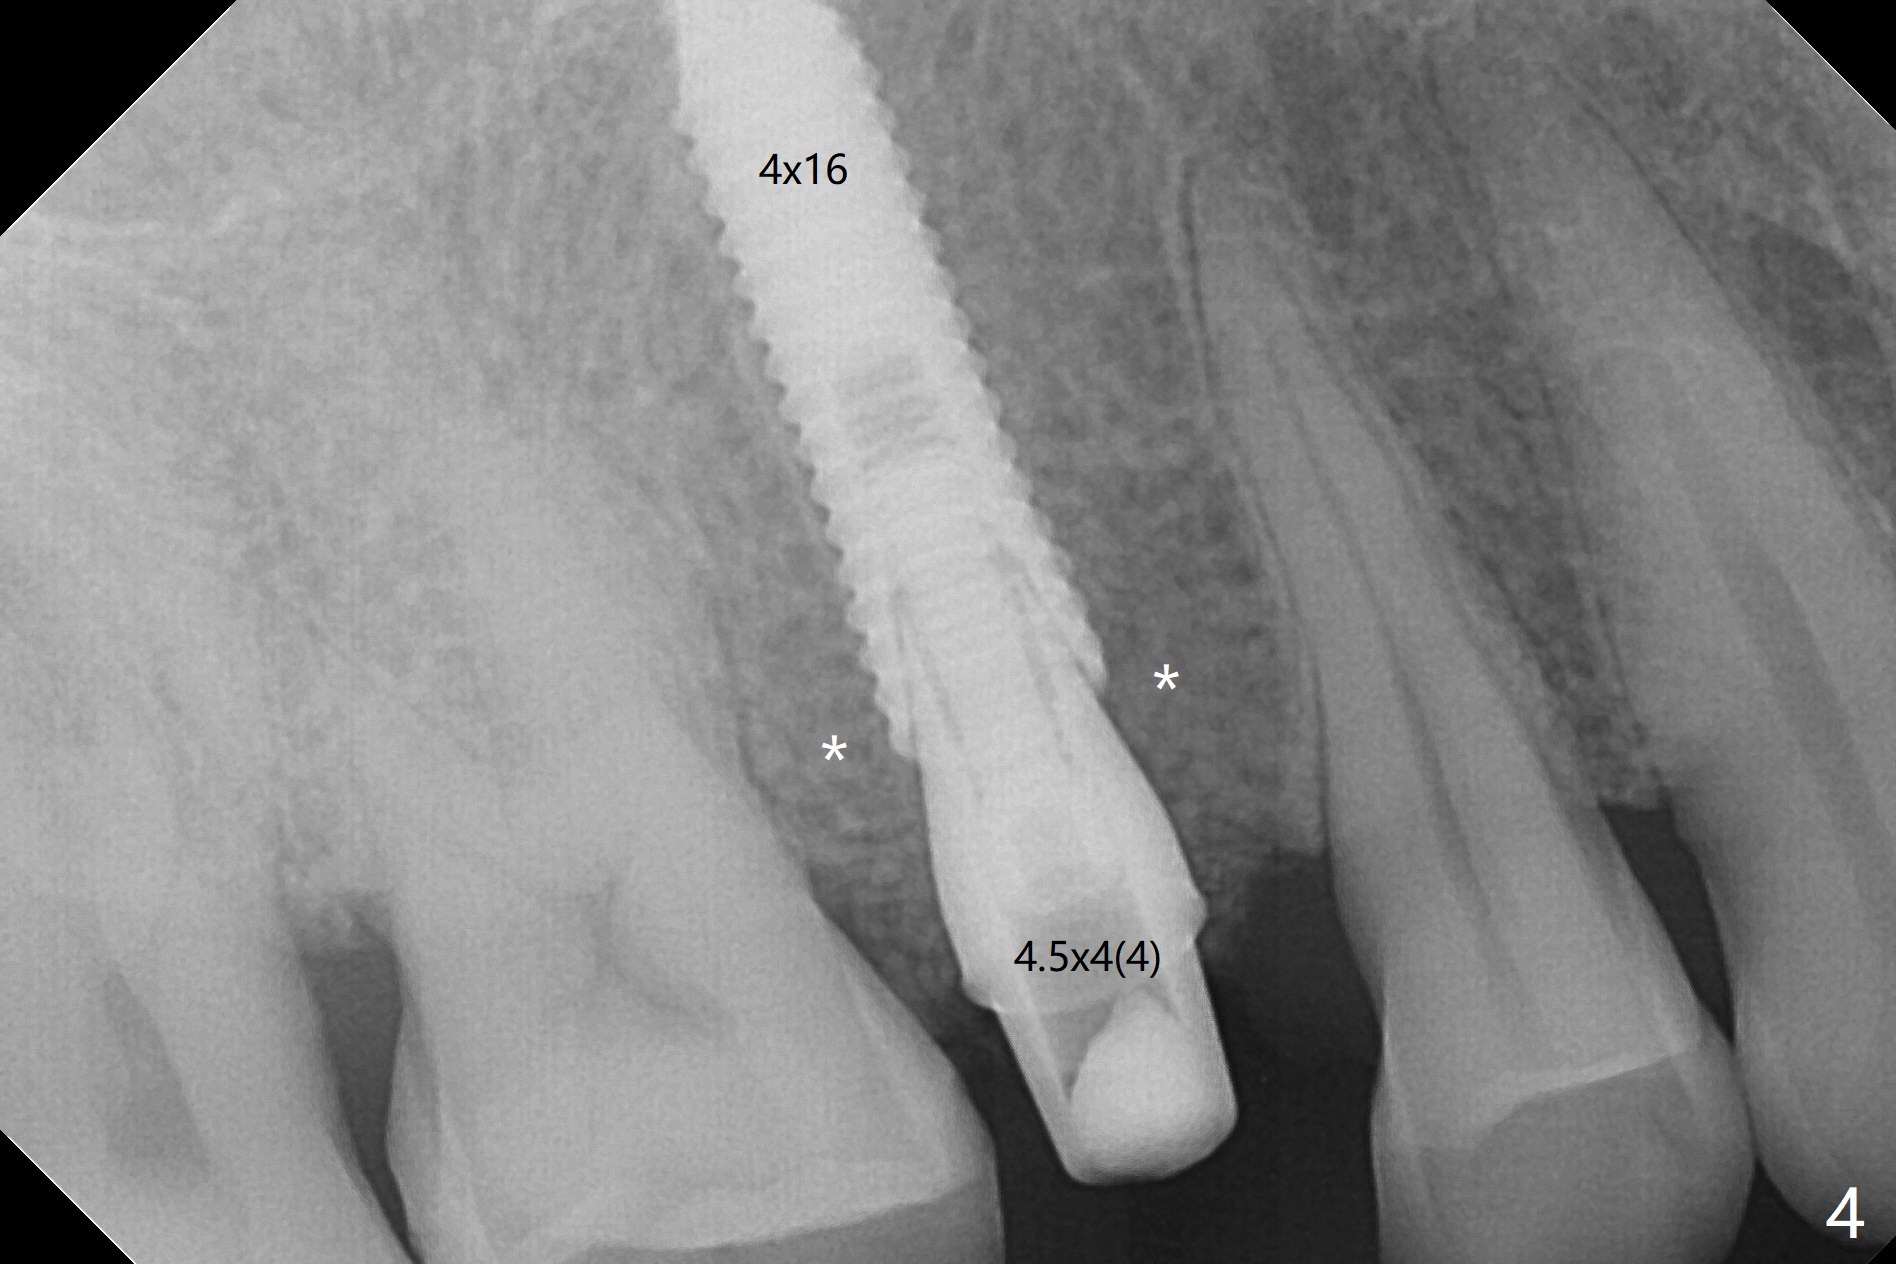

A 61-year-old man cracks the tooth #4 while chewing on a piece of chicken bone (Fig.1,2). Initial osteotomy appears to be able to hold a 16 mm long implant (Fig.3). After sequential osteotomy, a 4x16 mm implant is initially unable to be seated low enough for the buccal crest. Following packing the osteotomy with Vanilla Graft (.5-1 mm) and additional 2-3 mm depth of osteotomy, the implant is placed slightly apical to the buccal crest (Fig.4,5); with placement of Vanilla Graft (*) and a 4.5x4(4) mm abutment, an immediate provisional is fabricated to close the socket. The provisional is removed 3 months postop because of poor local oral hygiene (Fig.6,7). The gingiva is healthy 2-3 weeks later; it is easy to take impression (Fig.8).